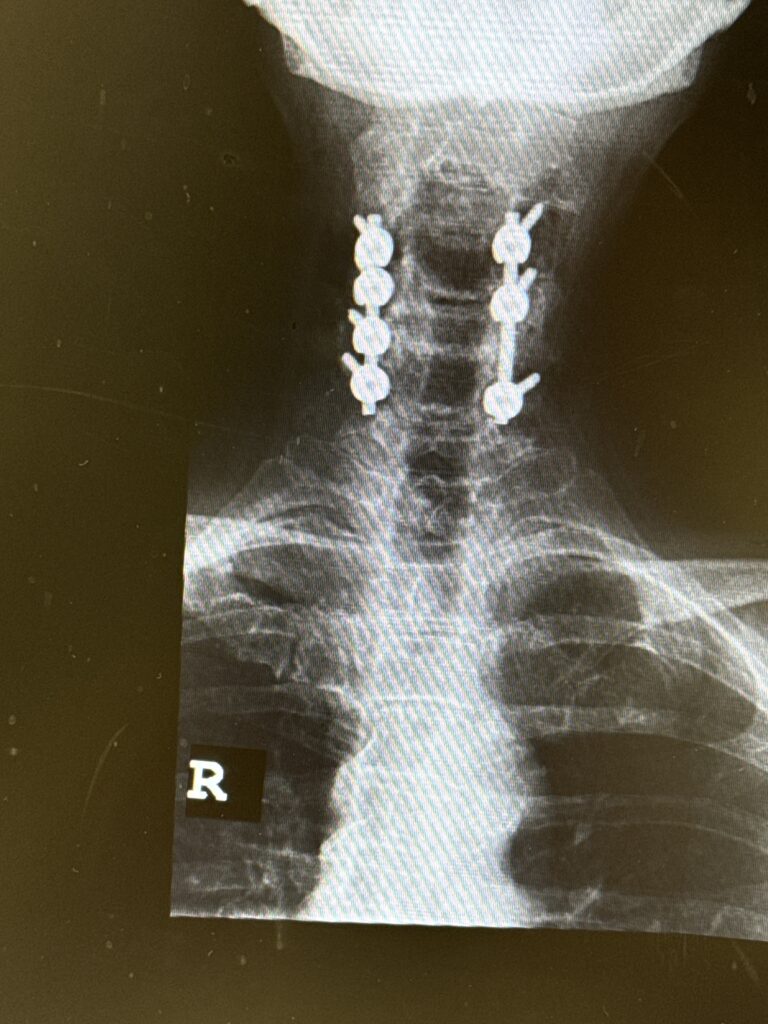

Patients may require an occipital-cervical fusion for both cranio-cervical and atlanto-axial instability, depending on the anatomy. Patients who have long segment posterior cervical fusions can sometimes […]

Here is a tough case: This is a 72 year-old male who presented with several months of progressive neck pain without symptoms of the arms or legs. […]